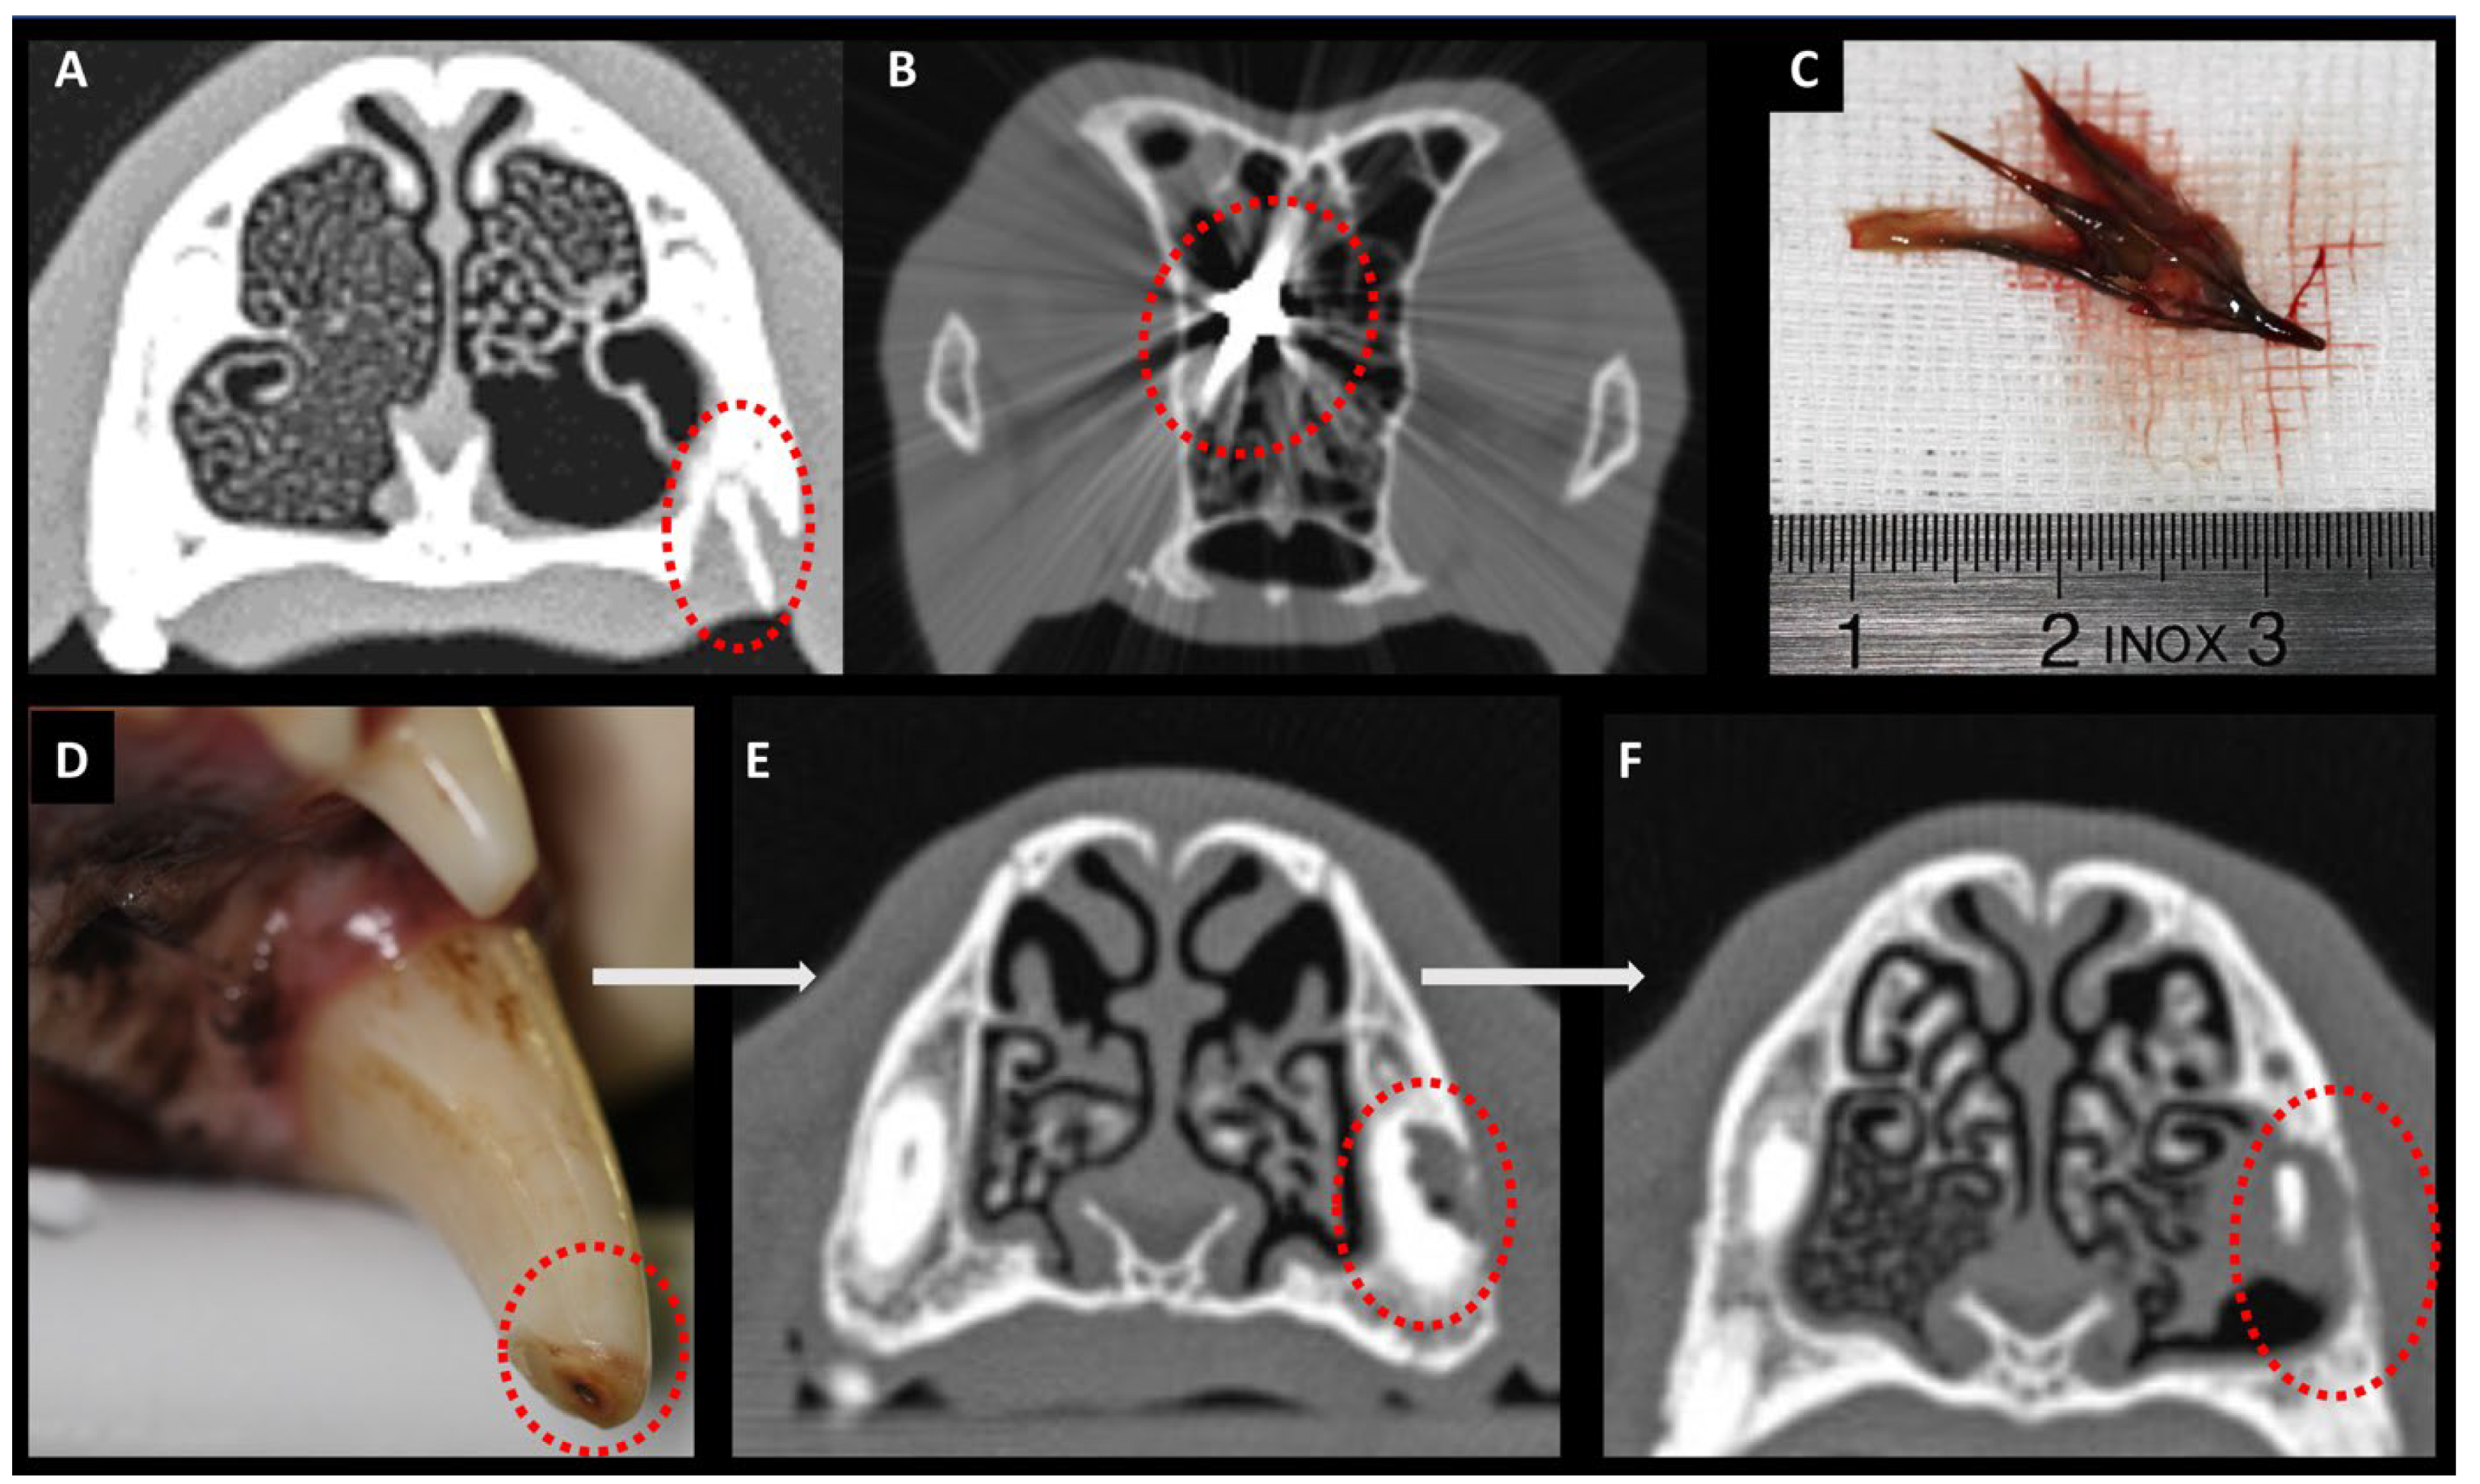

Eleven of the thirty dogs (37%) presented with additional nasal or perinasal pathology and were assigned to group sA. A plant-based nasal foreign body was diagnosed in 6/11 dogs (55%), dental root pathology in 4/11 dogs (36%), and an impression fracture of the frontal bone in 1 dog (1/11; 9%). In 9/11 dogs in group sA (82%), aspergillus infection was confined to the nasal cavity, whereas in 2/11 sA dogs (18%), frontal sinus involvement was also identified (Figure 5).

Diagnosis of an additional nasal cavity pathology was as follows (Figure 6): A nasal plant foreign body was diagnosed based on endoscopic findings, as CT did not provide meaningful information in this case. Conversely, bony changes—such as those resulting from dental root pathology or fractures—were detectable on CT but not visible on rhinoscopy.

Several nasal diseases may predispose dogs to developing nasal aspergillus infection as a secondary mycotic infection. The resolution of both the underlying nasal disease and the aspergillus infection following the treatment of these predisposing factors in our study supports the hypothesis of primary and secondary nasal aspergillosis. In our study cohort, dogs with sA presented with additional nasal diseases, including plant foreign bodies in 6/11 dogs, previous trauma with frontal bone fracture in 1/11 dogs, and dental root pathology in 4/11 dogs. According to the literature, nasal foreign bodies are associated with an increased risk of nasal mycoses [28], as are craniofacial trauma and fractures [29]. Dental root pathologies associated with nasal aspergillosis are mainly described in humans [30].

Consistent with the literature [31], rhinoscopy was the only diagnostic modality that enabled for detection of nasal foreign bodies in 6 of 30 dogs in our study. This was critical for assigning these dogs to the group of secondary aspergillosis. Ideally, CT examination is recommended for the detection of bony fractures. Regarding dental disease, it is important to emphasize that dental root pathology, when acting as a predisposing factor for secondary aspergillosis, does not necessarily present with a clinically visible oronasal fistula [5]. Such a dental root pathology may exist without breakthrough into the nasal cavity, underscoring the importance of cross-sectional imaging or dental radiographs [5]. Considering the results of this study, especially in dogs with exclusively nasal and non-sinonasal aspergillosis, CT or dental radiography should be performed to rule out secondary aspergillosis due to dental or bony pathology.